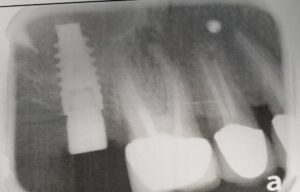

КТ діагностика ротової порожнини

Комп’ютерна томографія зубів – досконалий метод дослідження, який дозволяє лікарю визначати параметри будови зубощелепної системи, що дає більше інформації про аномальні патології. Це відносно нова методика діагностики в галузі стоматології. Але незважаючи на це, за короткий проміжок часу вона стала широко прийнятною.

Комп’ютерна томографія дозволяє отримувати тривимірні знімки щелепи і зубів. Завдяки цьому можна з великою ймовірність визначити точну проблему і призначити ефективне лікування. КТ дає можливість зрозуміти, що відбувається всередині зубів. Томографія стала невід’ємною частиною лікування серйозних травм щелепи, коли, в прямому сенсі її необхідно зібрати по частинах. Метод знайшов своє місце в усіх галузях стоматології.

Основними показаннями до даної діагностики є протезування і лікування деяких хвороб. Вона може бути застосована для імплантології, ендодонтії, пародонтології, ортодонтії та гнатології.

- У імплантології КТ необхідно зробити виміри щелепи, для установки імпланта.